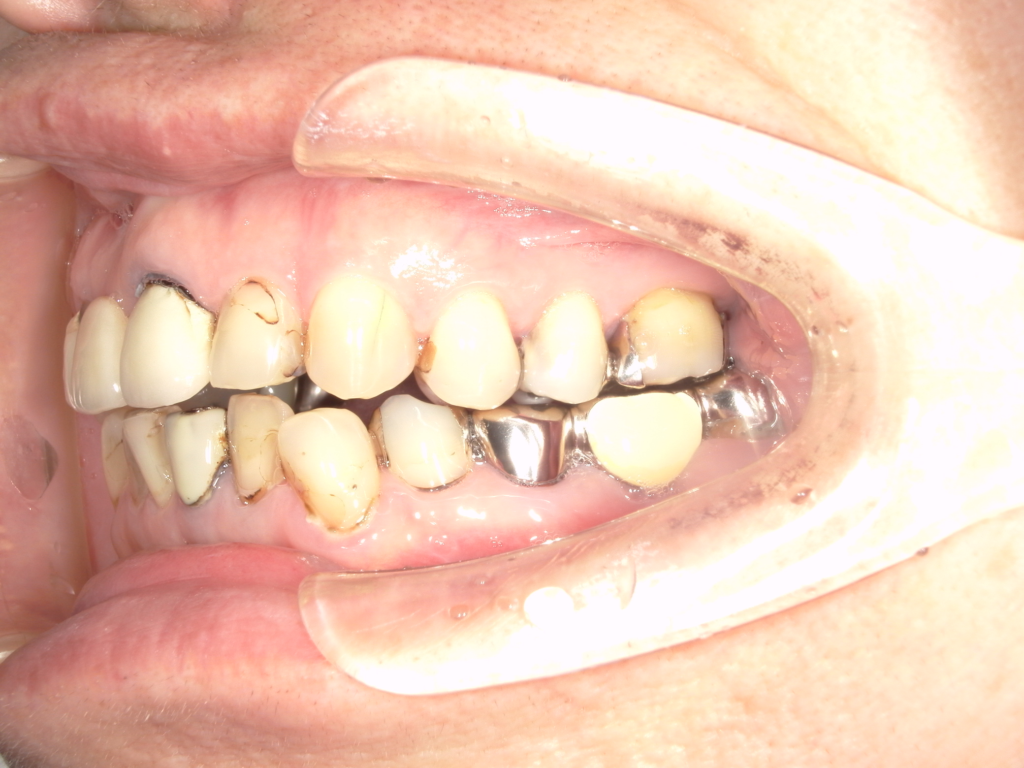

Y様インプラント実例 #44

左の上下の奥歯をインプラントで治療しています。

左下の奥歯は歯を抜くのと同時にインプラントの埋め込みを行っています。

被せものは上下、セラミックスで作っています。

治療前

治療後